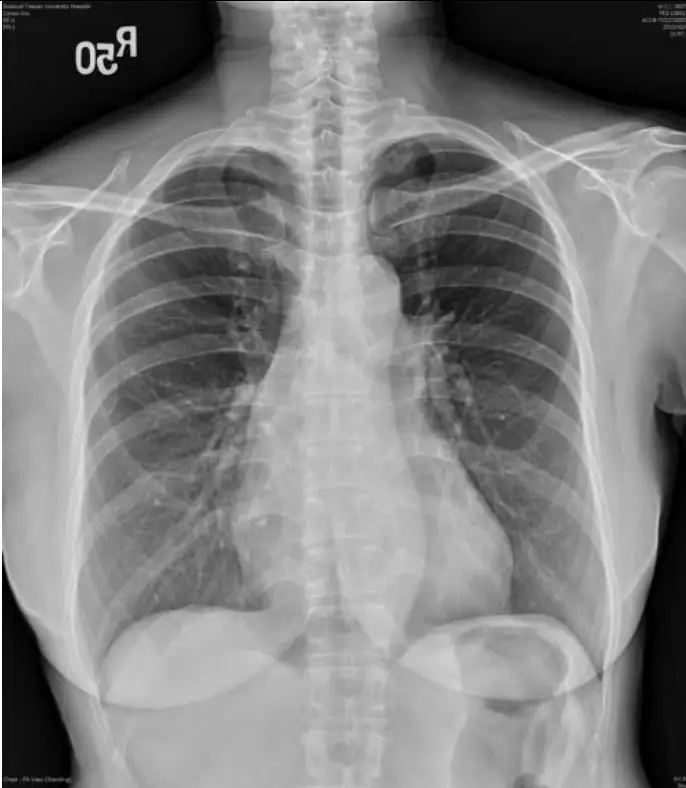

圖一:胸部X光(Chest X-ray, CXR) 正位胸部X光顯示:心臟大小在正常範圍,心胸比(cardiothoracic ratio)未明顯增加;肺部無肺水腫(pulmonary edema)或明顯充血性心臟衰竭(congestive heart failure)徵象;無胸腔積液(pleural effusion)。此影像不符合高血壓性心臟病(hypertensive heart disease)常見的心臟擴大表現,也不支持嚴重心臟衰竭。